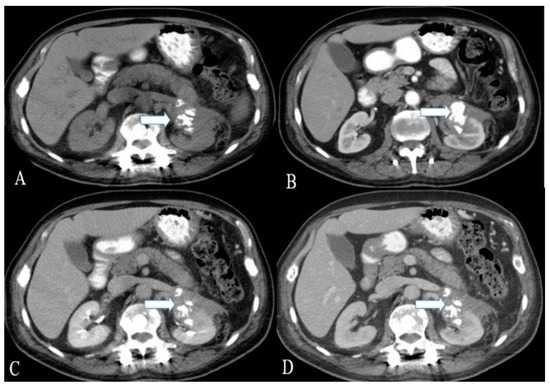

Figure 8. A 40-year-old female with urinary bladder NENs. Axial CT (A) pre-contrast and (B) delayed post-contrast images with coronal reconstruction (C) pre-contrast and (D) post-contrast reveal a 4.8 × 2.5 cm mass (arrows) at the proper aspect of the urinary bladder, showing faint peripheral calcification. Pathology revealed a neuroendocrine tumor of the urinary bladder.